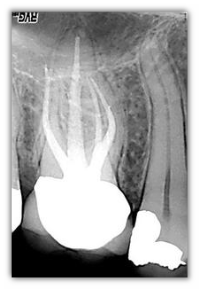

Una nuova tecnologia, un nuovo standard nell'immaginografia. Con la tecnologia supercmos vengono riuniti in un unico elemento tutti i vantaggi del CCD e del CMOS. Contrariamente al CMOS il supercmos utilizza tutta la superficie sensibile di ogni pixel per restituire l'informazione nella sua totalità. Rispetto al CCD il supercmos offre, a parità della qualità delle immagini, una più grande tolleranza alle sovraesposizioni (assenza dell'effetto blooming/saturazione del sensore). Il sensore ha una reazione simile a quella della lastra tradizionale.